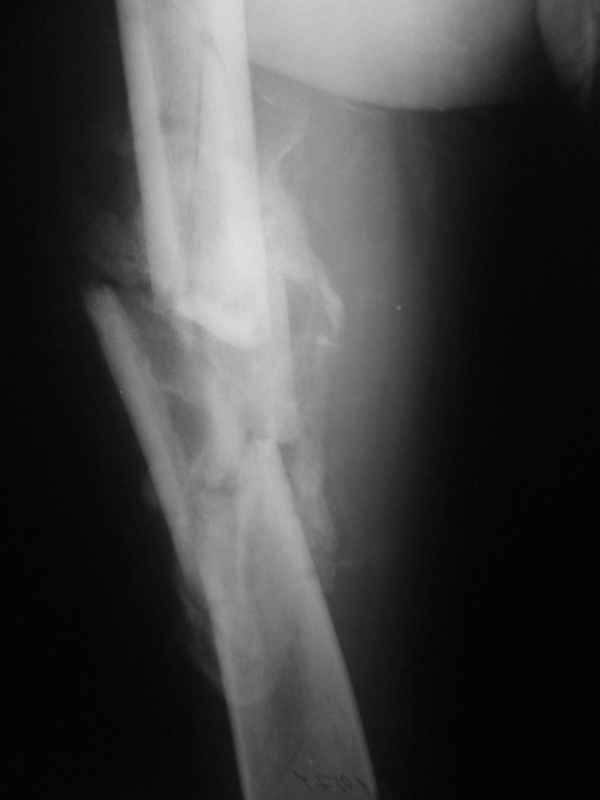

Неправильно срастающийся оскольчатый перелом бедра |

Пациент 39 лет. Травма в ДТП 2.5 месяца назад. Тяжелая сочетанная травма. ЗЧМТ. Тупая травма живота. Разрыв селезенки. Надрывы печени. Перелом бедра. При поступлении лапаротомия. Спленэктомия. Фиксация перелома бедра стержневым аппаратом. в последующем инфаркт мозга на фоне жировой эмболии. длительное нахождение на ИВЛ. Обширный пролежень в области крестца. и т.д.в настоящее время состояние больного стабилизировалось. активизирован на ходунках.имеется деформация бедра, укорочение 10 см. гранулирующий пролежень в области крестца. патологической подвижности в зоне перелома не отмечается.Оптимальные сроки проведения реконструктивной операции на бедре? Сейчас? Или после окончательного сращения?

А откуда такое укорочение взялось, 10см? По представленному фрагменту рентгенограммы понять трудно. В любом случае, если состояние пациента позволяет оперировать сейчас, зачем откладывать операцию до формирования монолитного сращения?

Конечно, снимки для планирования надо нормальные, не такой огрызок.

Можно закрыто мобилизовать отломки, наложить дистракционный аппарат, восстановить ось и длину, да и заштифтовать, на всякий случай с антибиотиковым цементным покрытием.

Попробовать-то можно. И просто руками "об колено", а то и наложить аппарат, приложить флексионные и ротационые усилия прямо за разъединенные секции.

Если уж никак, то сделать чрескожную остеотомию.

Но если картинки недавние, IMHO должно получиться закрыто разобщить.